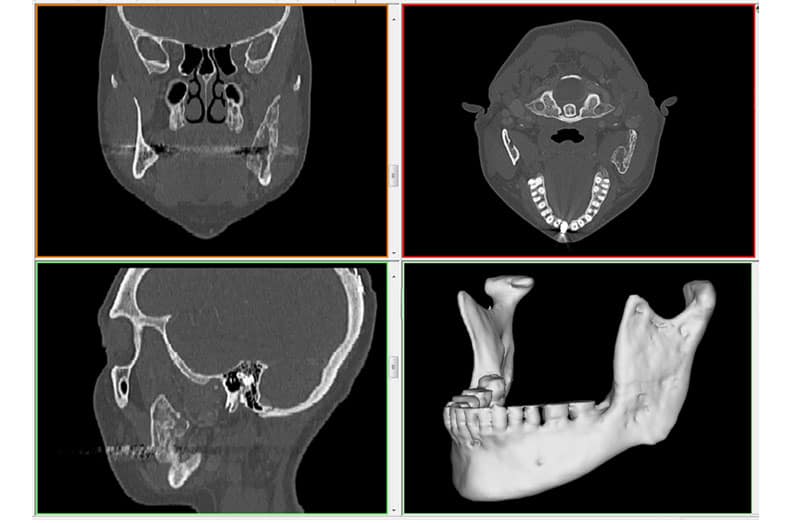

Virtual Surgical Planning (VSP) is a pre-operative planning method that involves the visualization of a surgical procedure using 3D imaging computer software. The central patient benefit of using VSP is that it assists your surgeon in predefining each step of the surgical procedure including goal planning, bone segment navigation, and ensuring facial symmetry.

VSP utilizes medical image data to accurately plan the surgery so that the surgeon can then transfer that plan to the patient using customized 3D printed surgical guides.

If you are a candidate for VSP the first step will be to undertake a comprehensive initial workup session. This session will include taking all 3D facial and intraoral images, measurements, plain films, study models, midline notations, occlusion class notation, a bite registration, and a cone beam CT scan. A cephalometric analysis is then performed to show the spatial relationships between dental and skeletal elements.

The data collection is then digitized and virtual 3D models are created to simulate the planned surgical movements and outlined patient goals based on the pre-op analysis. The VSP software shows different colors for different sections of the skull, making it easy to see what goes where and in what order.